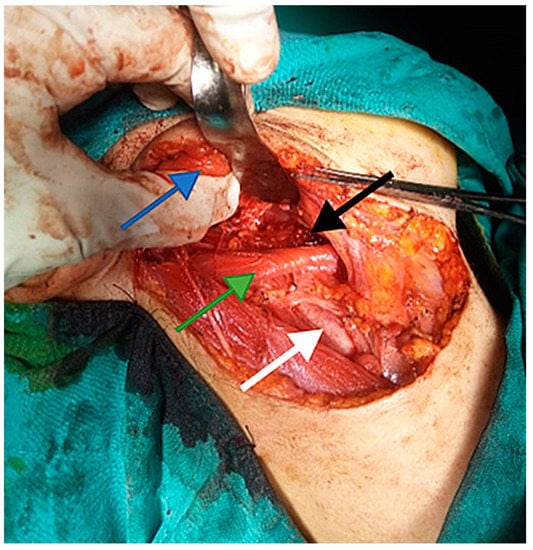

6. Differential Diagnosis of the Extracranial FNS

7. Therapeutic Strategies in the Management of FNS Extracranial Segment